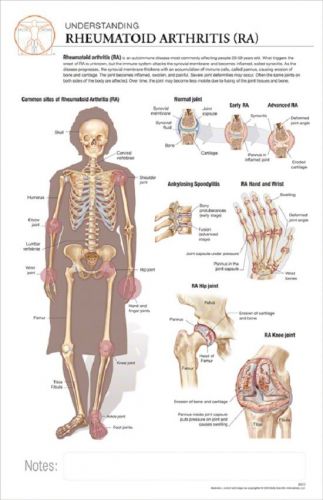

11 x 17 Post-It Disease Chart: RHEUMATOID ARTHRITIS